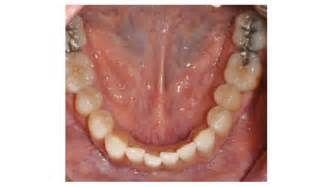

3.頜下間隙感染:智齒冠周炎或者下頜磨牙根尖周炎久治不愈,細(xì)菌通過頜下淋巴結(jié)擴(kuò)散到頜下三角,出現(xiàn)下頜部腫脹疼痛,舌下腫脹,也可出現(xiàn)張口困難,需要緊急進(jìn)行手術(shù)排膿引流。2.咀嚼肌下間隙感染:當(dāng)?shù)谌パ拦谥苎滓卜Q為智齒感染時(shí),如果沒有時(shí)間進(jìn)行治療的話,細(xì)菌容易擴(kuò)散到咀嚼肌下間隙,引起感染,可出現(xiàn)半個(gè)臉腫脹疼痛,也可出現(xiàn)張口困難,需要緊急手術(shù)排膿抗菌消炎處理,不然的話,有可能引起下頜骨骨髓炎。